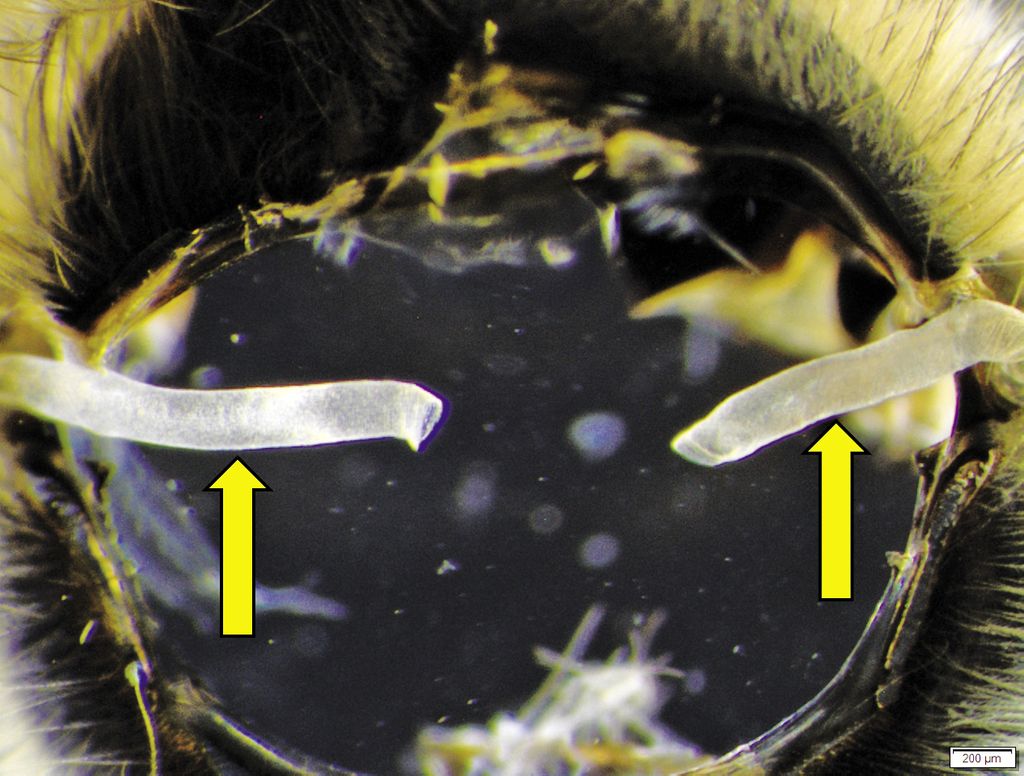

Acarapis woodi (foto 1) este un parazit obligatoriu care trăiește și se reproduce în prima pereche de tuburi traheale (foto 2, foto 3), a fost observat și la nivelul sacului aerian de cap, tors și abdominal. Parazitul este dioic.

Femela adultă intră în inelele traheale prin prima pereche de spiracule toracice (albina are 10 perechi de spiracule, dintre care 9 perechi sunt vizibile pe corp), deoarece numai acestea au un diametru suficient de mare.

Foto 2. Prima pereche de tuburi traheale ale albinei.

Fotograf Andrzej Bober.